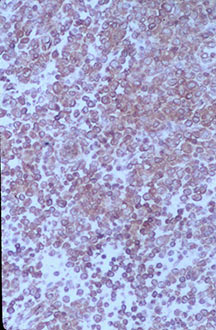

Microscopic Pathology

- Langerhans cell is diagnostic and clonal proliferation

- Nuclei show prominent nuclear groove (coffee-bean)

- Also composed of eosinophils and other inflammatory cells (non diagnostic component)

- Ratio of inflammatory cells to Langerhans cells varies

- Mitotic activity low

- Eosinophils dominate some areas forming diffuse sheets, excluding Langerhans cells

- Birbeck Granules: Electron Microscopy demonstrates granules that often take the form of a tennis raquet and form from complex invaginations of the cell membrane

- Vimentin, CD1 and S-100 positivity